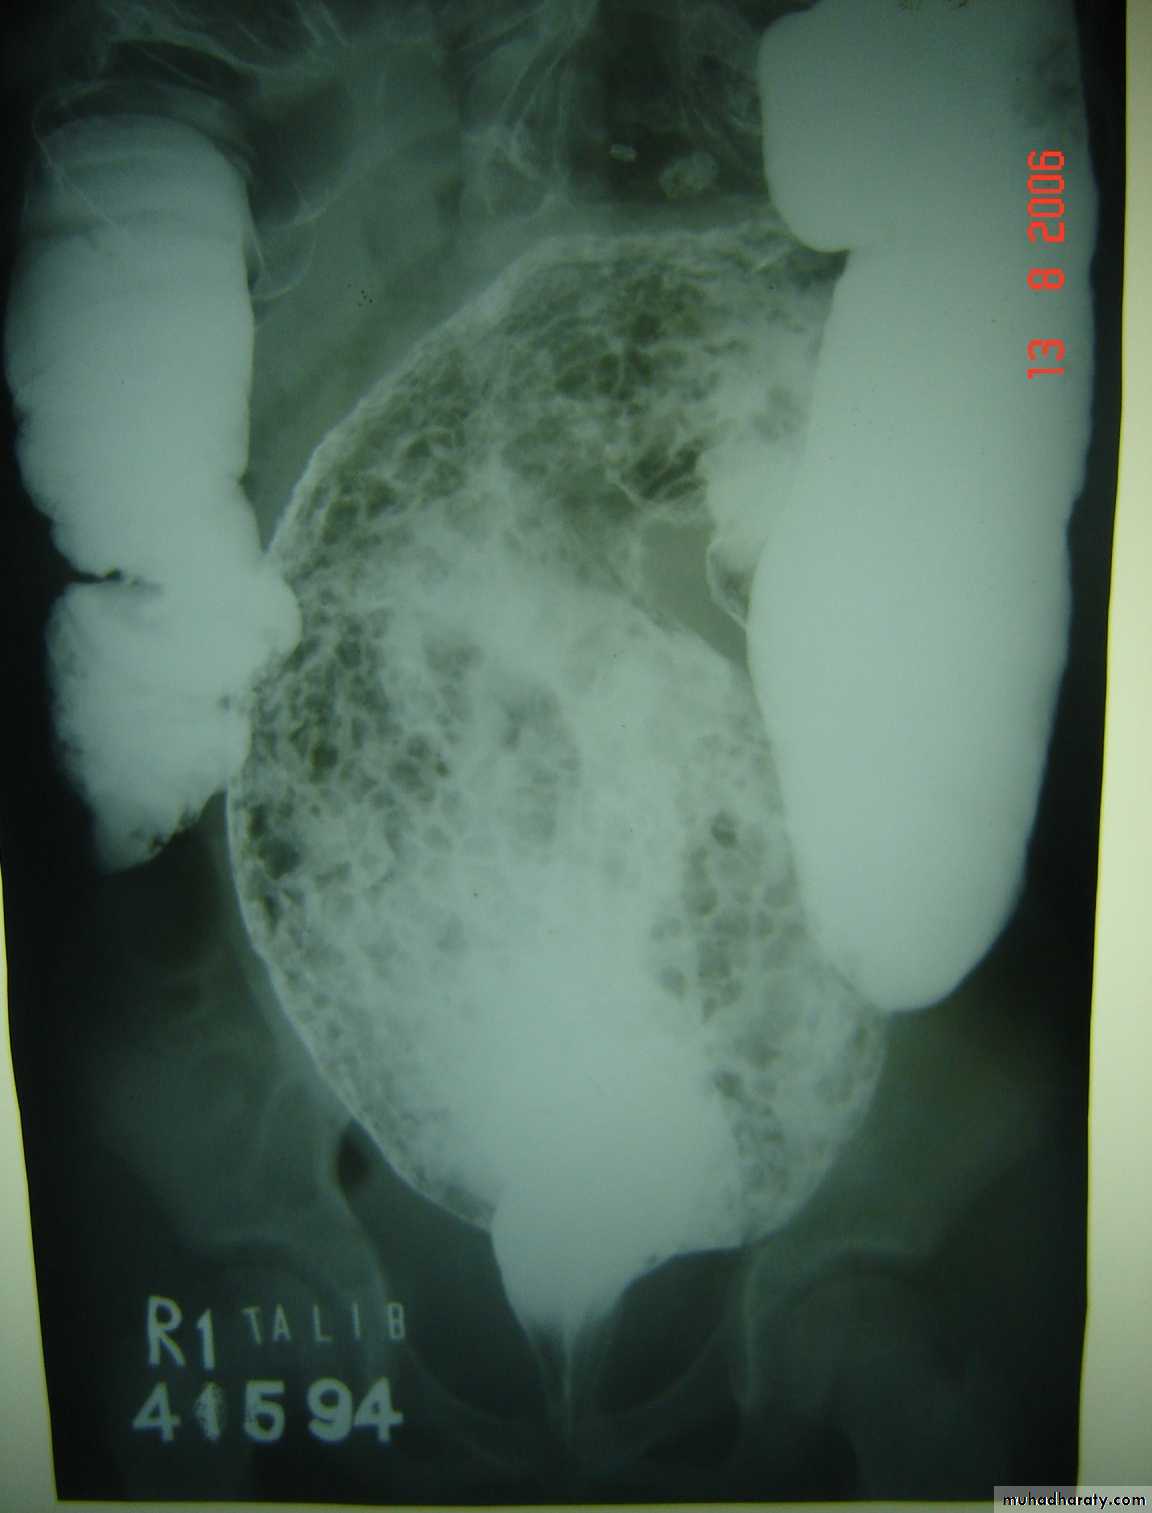

Oesophageal Atresia and Tracheo-Oesophageal Fistula,